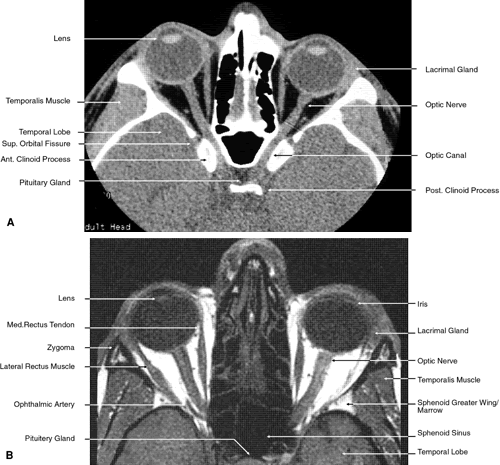

Fig. 24. Axial images at the level of superior orbit. A. Computed tomography scan. B. T1-weighted magnetic resonance imaging.

Fig. 25. Axial images at the level of tendon of the superior oblique. A. Computed tomography scan. B. T1-weighted magnetic resonance imaging.